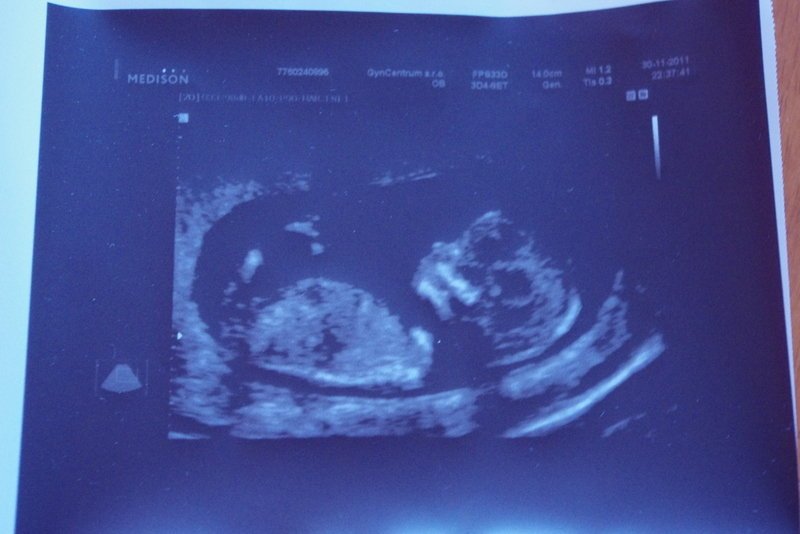

Ke gynekologovi si jedu pro výsledky krve a na ultrazvuk v prvním trimestru. Všechno je v naprostém pořádku, plodová voda se vůbec neřeší. Mám špatný pocit z ultrazvuku, ale aspoň viděl mimčo můj muž, který mě jinak jako těhotnou vůbec nevnímá. Není to na mě vůbec poznat, nestěžuji si na nic a doma i v práci všechno funguje jako doposud. Tak teď vypadal, že už to začíná víc vnímat :-) Nemůžu se na něj moc zlobit, sama si moc těhotná nepřipadám. Mám jen takovou ještě většíradost ze života a těším se, že na jaře budeme mít přírůstek.